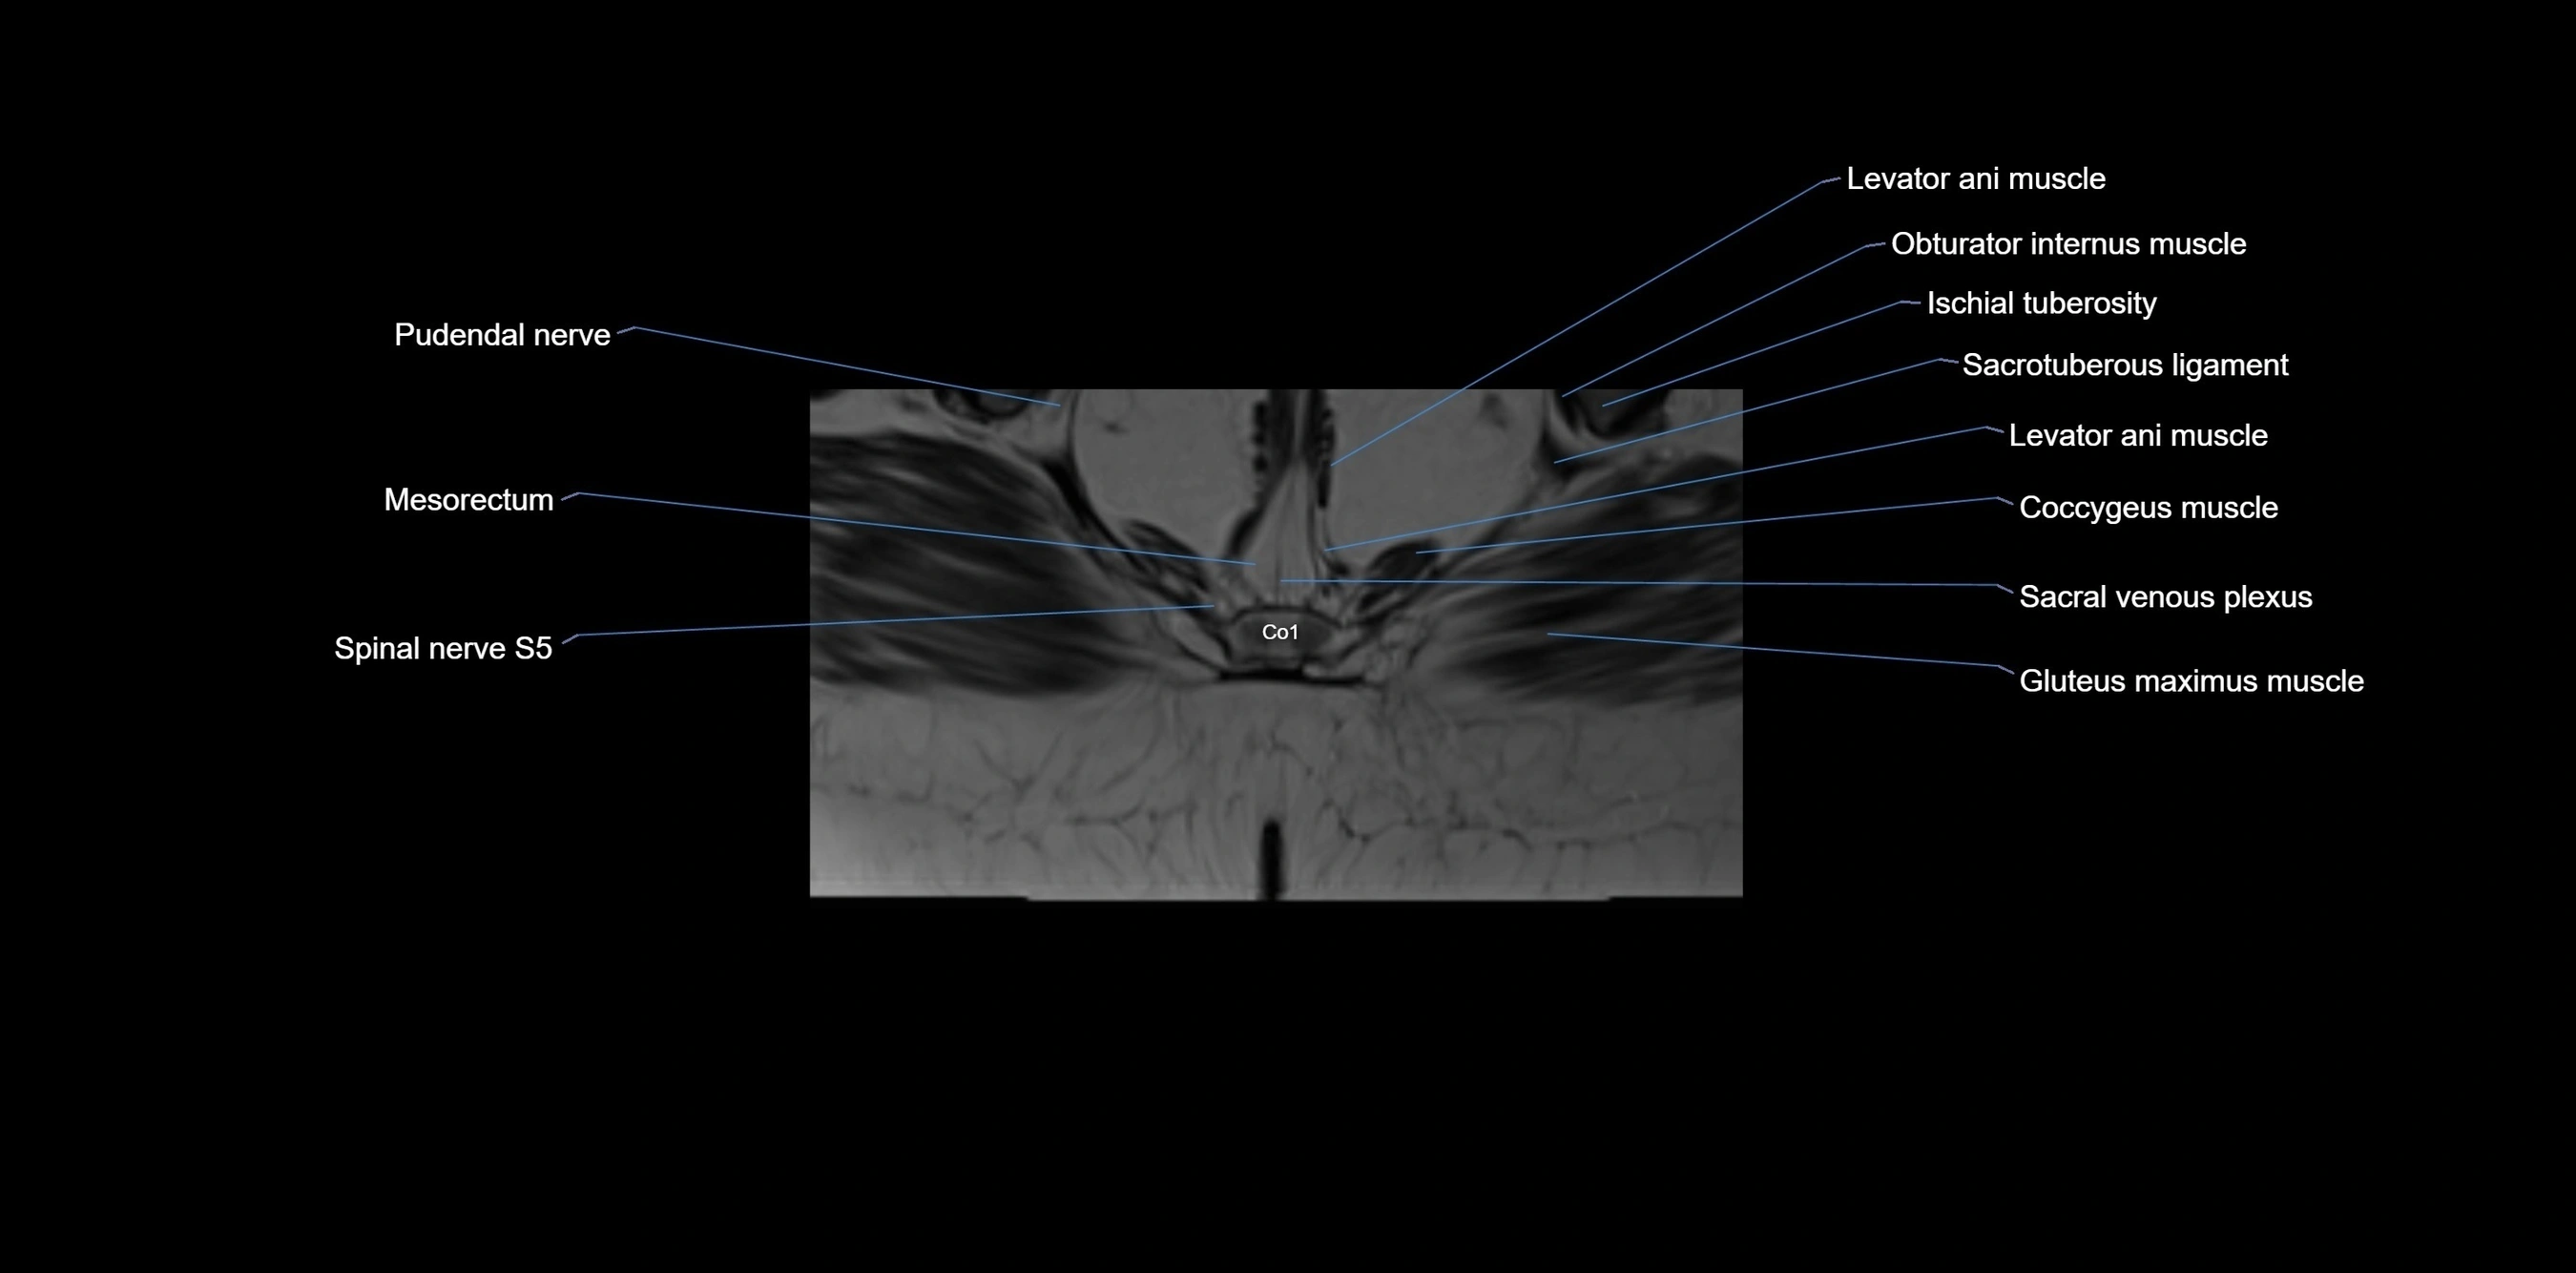

MRI Appearance

T1-weighted images:

• Cortical bone appears very low signal (dark); marrow shows intermediate signal

• Iliac fossa fat is bright against low-signal cortex

T2-weighted images:

• Cortical bone remains dark

• Marrow signal varies depending on fat content; edema or tumor shows hyperintensity

STIR:

• Suppresses fat, making bone marrow edema, fractures, or infiltrative lesions appear bright

• Excellent for trauma, sacroiliitis, and metastatic evaluation

T1 Fat-Saturated (Pre-contrast):

• Marrow: intermediate signal, fat suppressed

• Useful for detecting subtle marrow abnormalities adjacent to iliac cortex

T1 Fat-Saturated Post-Contrast (Gadolinium):

• Enhances vascularized structures, marrow pathology, tumors, and inflammatory changes

• Highlights soft tissue or bone invasion in pelvic neoplasms

MRI Non-Contrast 3D Imaging:

• Provides 3D morphology of iliac wing, crest, and articulations

• Used in preoperative planning for pelvic surgery and trauma reconstruction

MRI image

image